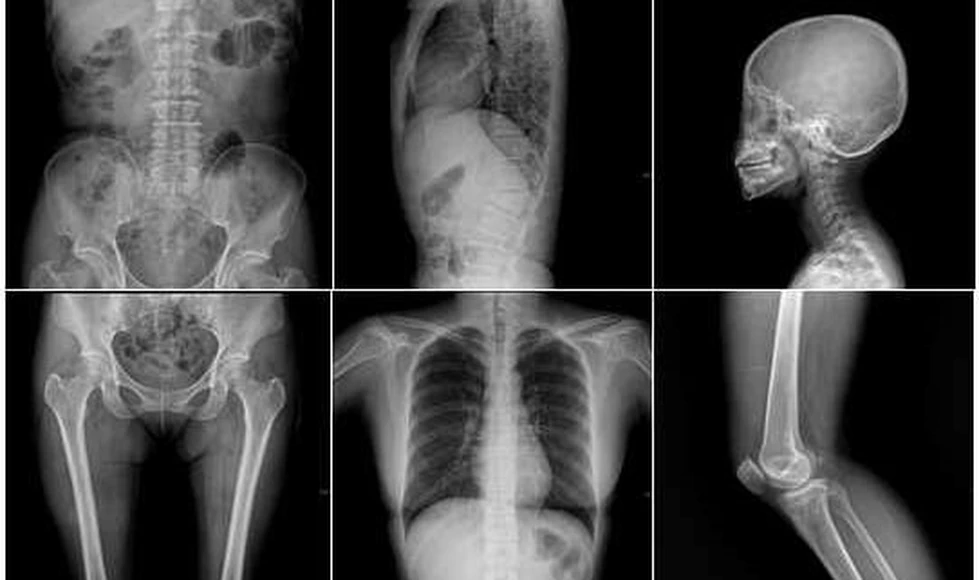

Penetración: Los rayos X pueden atravesar tejidos blandos y estructuras sólidas, pero son absorbidos en diferentes grados por diferentes materiales. Por ejemplo, los huesos absorben más rayos X que los tejidos blandos, lo que permite obtener imágenes contrastadas en radiografías.

En medicina, los rayos X se emplean en radiografías para detectar fracturas óseas, evaluar la salud pulmonar, identificar problemas dentales, entre otros. Las tomografías computarizadas (CT) utilizan múltiples rayos X para generar imágenes tridimensionales de órganos internos. En la industria, se usan para inspeccionar la calidad de materiales y componentes.